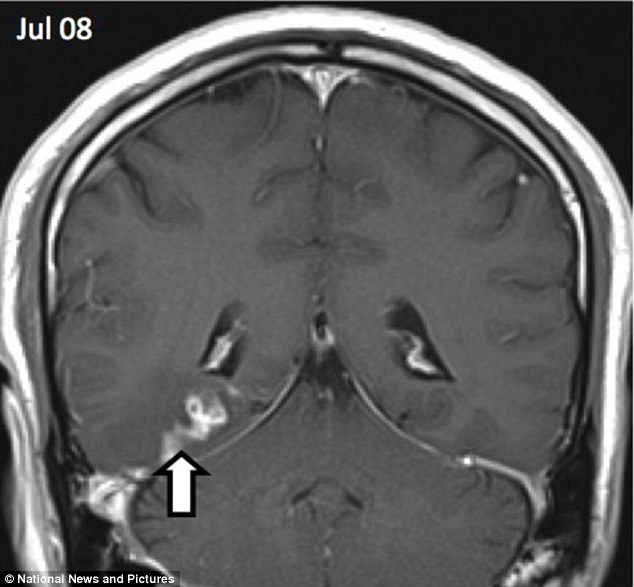

Pacientul este din Marea Britanie şi prima scanare la RMN a fost realizată în anul 2008.

În decursul a 4 ani, viermele s-a deplasat de pe partea dreaptă a creierului spre partea stângă, pe o distanţă de 5 cm.